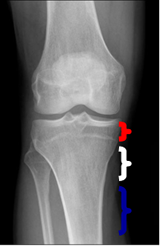

LONGITUDINAL: (Fig 16).

Fig 16. Localización longitudinal.

Rx AP. Zona roja: Epífisis, Blanca: Metáfisis y Azul: Diáfisis.